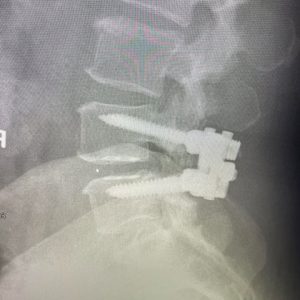

The patient in the images had mostly back pain that was worse with standing for 5 minutes associated with her L4-5 instability. Therefore, she was best served with a laminectomy and fusion surgery. Don’t settle for a one-size-fits-all approach to surgery. Talk to your surgeon about all the options, and if you don’t understand completely, seek out a second opinion.